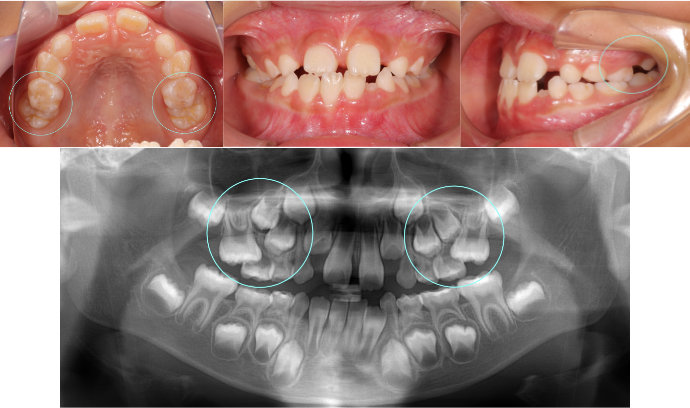

| Case11 |

| 受け口 および 右上の乳臼歯が早期に抜けたことにより、その後ろにある6歳臼歯が前方にずれている。そのため、6歳臼歯の直前にある永久歯が生える隙間がない。 |

| <治療前> |

| <治療後> |

| 主訴 |

前歯が反対になっている |

| 診断名 |

上顎右側第二乳臼歯の早期喪失による上顎右側第一大臼歯の近心転位、それに伴う上顎右側第二小臼歯の萌出スペース不足を伴う反対咬合

|

| 年齢 |

10歳 |

| 使用装置 |

マルチブラケット装置 |

| 抜歯部位 |

永久歯の抜歯は無し |

| 治療期間 |

3年8か月 |

| 治療費概算 |

検査・診断料:5万円+税 装置・技術料:25万円+税 来院ごとの処置・管理料:5,000円+税 保定装置料:5万円+税 |

| リスク・副作用 |

特になし |